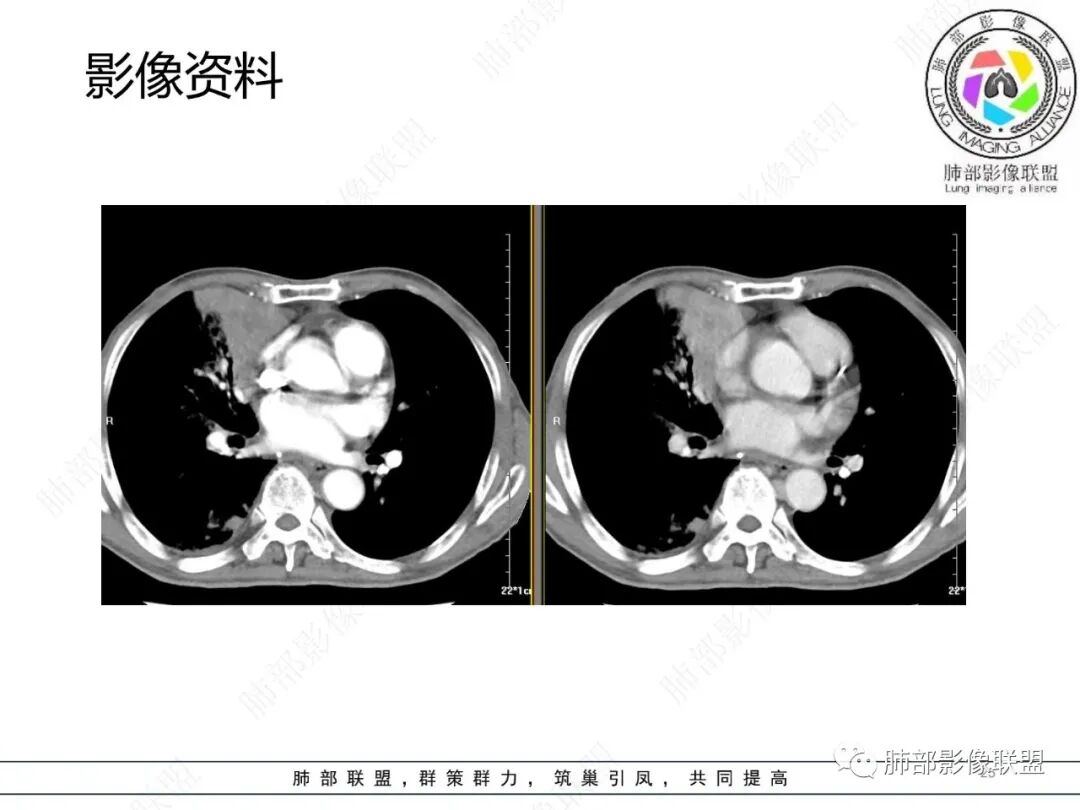

影像资料

2.胸部CT: 右肺病灶,主要累及右肺上叶前段、右肺中叶内侧段及右肺下叶背段,片状影及结节影,实性密度为主,部分磨玻璃晕,密度不均,散在钙化,其中上叶前段支气管闭塞,隐约见钙化突入。未见明确“硬树芽”或“拐枣征”。主要呈延迟强化,其间低密度区疑坏死或粘液成分。纵隔内见多组淋巴结肿大环形强化,部分钙化。

3.综合分析:影像病灶集聚(右肺上叶前段、右肺中叶内侧段),实性密度为主,钙化及液性密度区,淋巴结环形强化等,较常见于继发性肺结核,或伴其他混合感染(支气管阻塞)。尽管未见典型硬树芽。